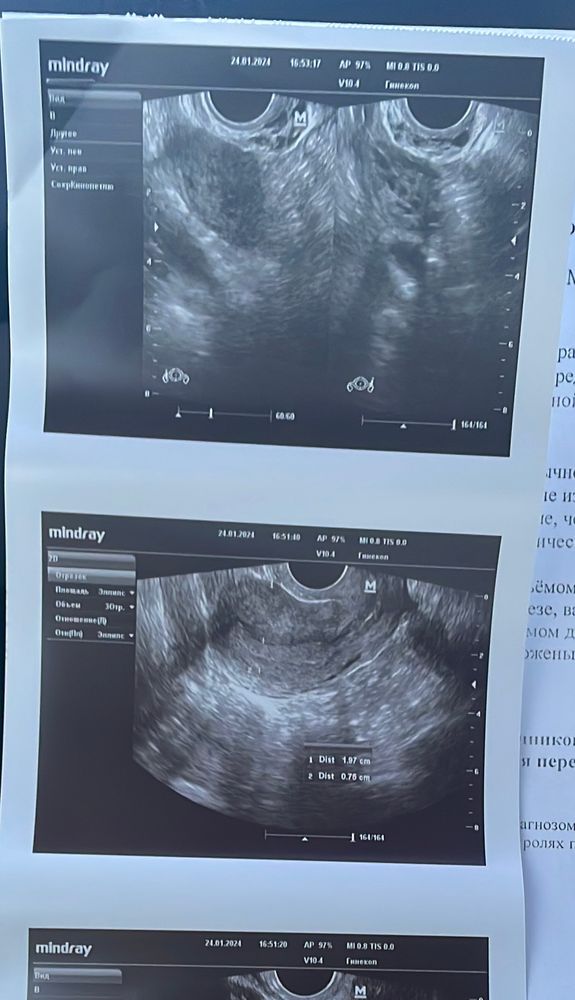

У меня сегодня нашли жт в левом яичнике, а вот плодного нет( поздняя овуляция и плавающий цикл. Вот и вся надежда. Изображение